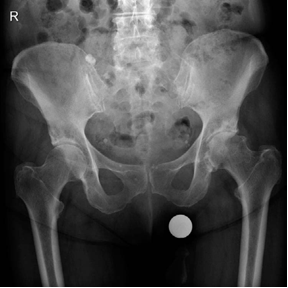

Structured Oral Hip Examination Question 4 EXAMINER : These are the radiographs of a 78-year-old lady who has…